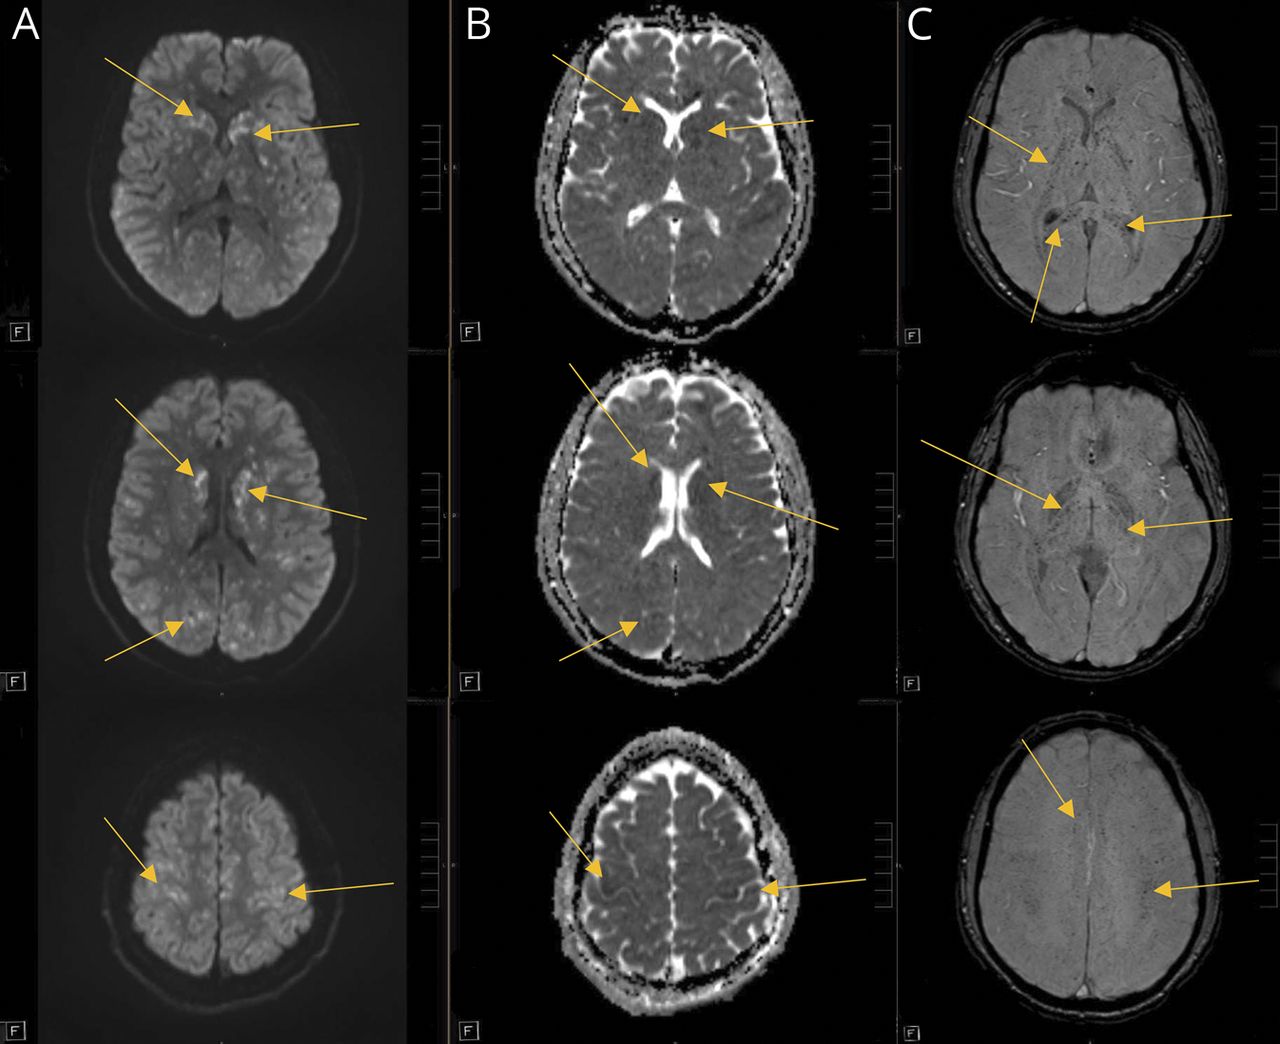

符合最初的本地化双边半球,MRI大脑没有对比postfall第一天显示广泛的证据bihemispheric受伤,广泛地分散点状的疫源地的扩散限制(图1)和大量的证据bihemispheric microhemorrhages (图2)。

(Diffusion-weighted成像hypertintensities驾车,)和表观扩散系数序列hypointensities (ADC, B)显示弥漫性点状的疫源地的扩散限制,与susceptibility-weighted成像hypointensities显示许多microhemorrhages(瑞士,C)。